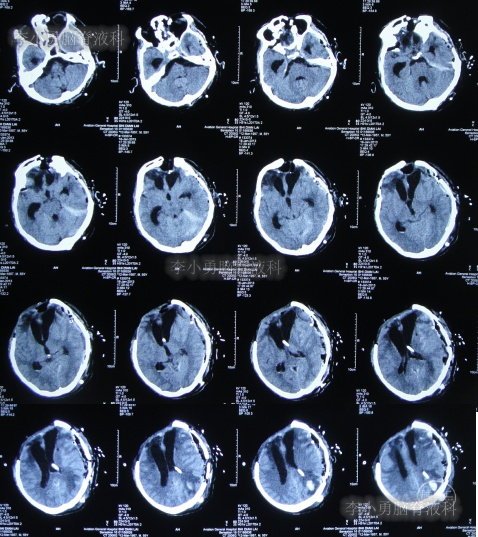

2013年1月30日(入院治疗91天),引流出血红色脑脊液(图-17)。

2013年1月31日(入院治疗92天),查头颅CT示脑室进一步缩小,骨窗塌陷(图-18)。

图-18:2013年1月31日头颅CT

继续治疗1个半月,期间4次(2013年2月15日、2013年2月27日、2013年3月5日、2013年3月11日)查头颅CT(图-19、图-20、图-21、图-22)均示脑室在不断的变好。

图-19:2013年2月15日头颅CT

图-20:2013年2月27日头颅CT

图-21:2013年3月5日头颅CT

图-22:2013年3月11日头颅CT

2013年3月12日(入院治疗132天),拔除了头部外引流管(图-23)。

图-23:2013年3月12日头颅CT

2013年3月15日(入院治疗135天),查头颅CT示脑室周水肿减轻(图-24)。

图-24:2013年3月15日头颅CT